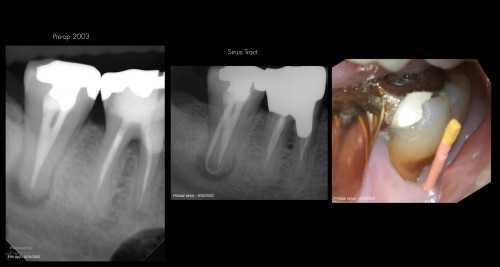

1st Post

By Bobby Nadeau / July 10, 2018

There it is, 1st post on TDO University. 2.7 Necrotic/CAA. Small mouth + limited opening. 2 […]